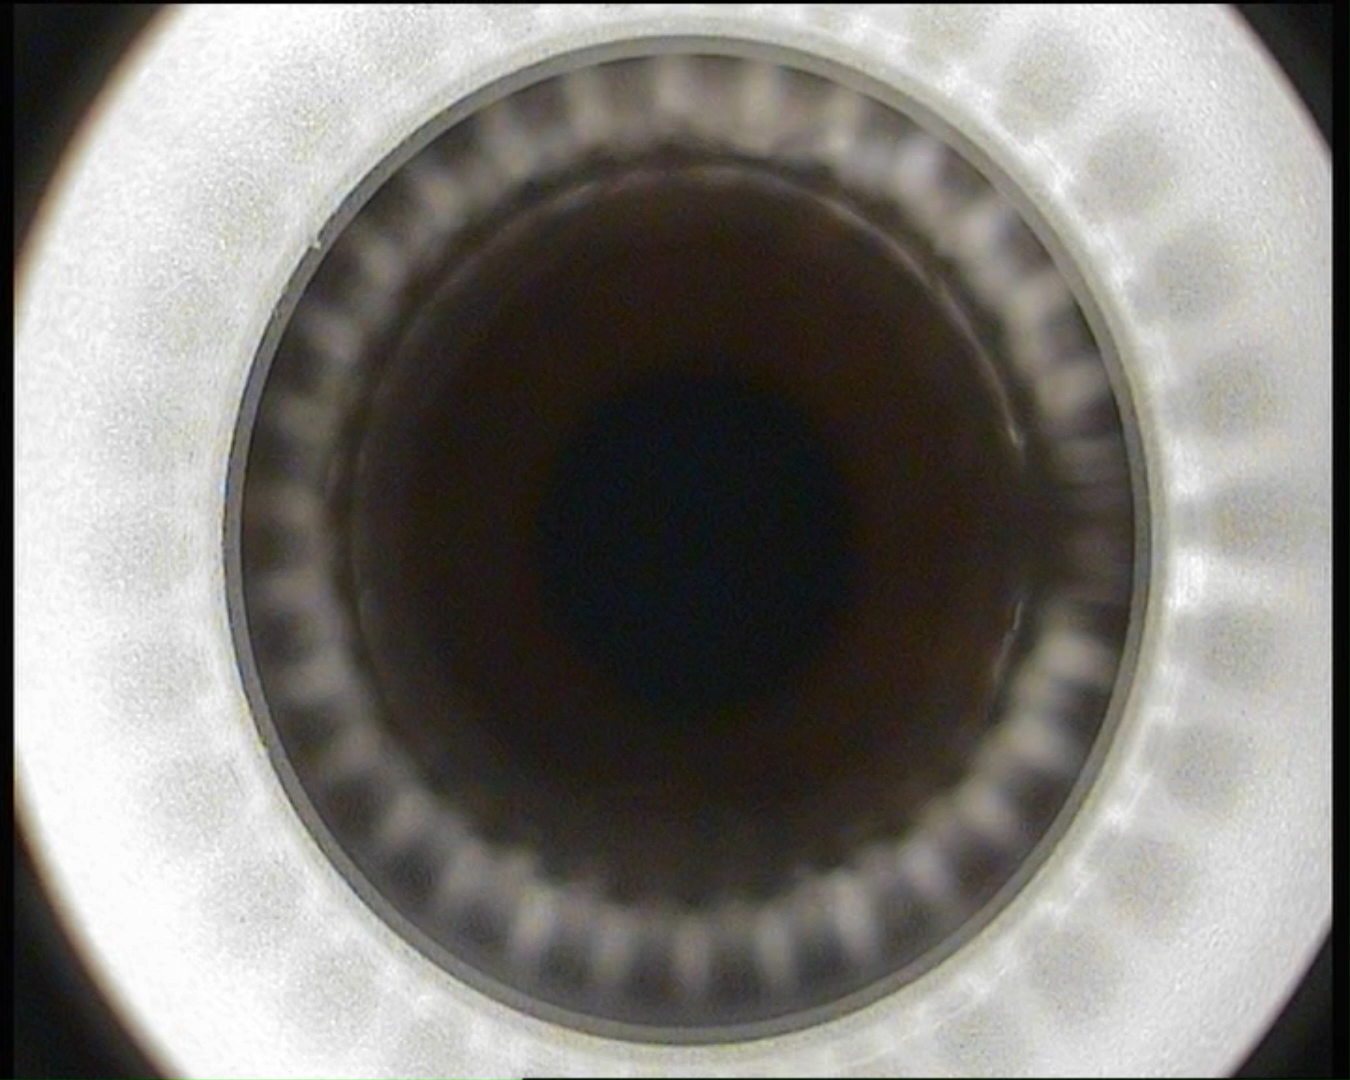

飞秒手术对中心的疑问,术中调来调去,好像调了个寂寞。。。。。。 最后又落到开始的点上了